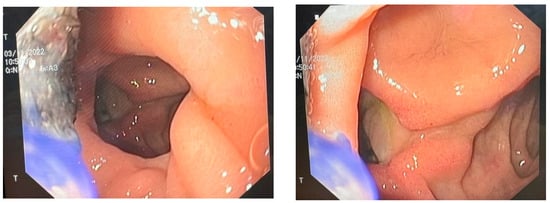

The E-VAC DI-DII kit was removed on the 21st postoperative day of the second intervention, and the DI defect was found to be closed [Figure 4]. The patient was recovering well with signs of weight gain and, therefore, was determined to be cured and discharged [Figure 5].

Figure 4.

Completely closed duodenum.